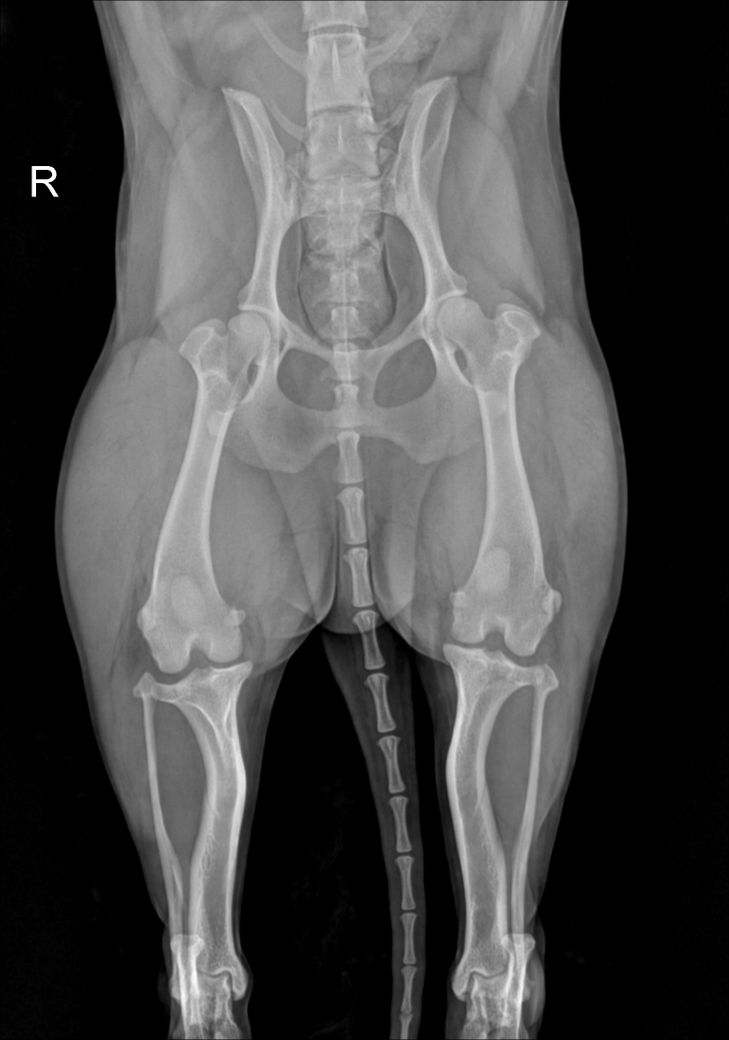

제시된 사진에서는 우측 슬과절 관절낭의 종창 즉, 물이 찬 현상이 있습니다. 이런 현상이 일어나는 원인에는 인대의 문제일 수도 있고, 면역계통의 문제일 수도 있습니다. 특히 이런 물이 찬 상태는 개에서는 십자인대가 손상이 있을때 나타나는 주요 현상으로 스테로이드와 같은 소염작용이 있는 약물을 투약하면 일시적으로 개선될 수 있습니다. 다만 십자인대가 점차 뻣뻣해지면서 향후 십자인대 단열이 발생할 가능성이 높아지니 TPL을 낮추는 수술을 선행적으로 해줄 필요가 있습니다.

사진상에서 실제 좌측에 비해 우측의 TPL이 증가한 양상이 명확하게 관찰되니 주치의와 상담 후 TPLO 고려하시기 바랍니다. ㅈ